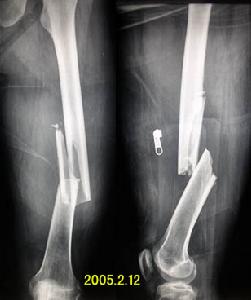

兒童的股骨幹骨折可能為不全或青枝骨折;成人股骨幹骨折後,內出血可達500-1000ml。可發生斜形、螺鏇形或青枝骨折。骨折發生的部位以股骨幹中下1/3交界處為最多,上1/3或下1/3次之。骨折端因受暴力作用的方向,肌群的收縮,下肢本身重力的牽拉和不適當的搬運與手法整復,可能發生各種不同的移位。股骨幹上1/3骨折時,骨折近段因受髂腰肌,臀中、小肌及外鏇肌的作用,而產生屈曲、外展及外鏇移位;遠骨折段則向後上、內移位。

股骨幹中1/3骨折時,骨折端移位,無一定規律性,視暴力方向而異,若骨折端尚有接觸而無重疊時,由於內收肌的作用,骨折向外成角。 股骨幹下1/3骨折時,由於膝後方關節囊及腓腸肌的牽拉,骨折遠端多向後傾斜,有壓迫或損傷膕動、靜脈的危險,而骨折近端內收向前移位。

股骨上1/3骨折後,近折段受骼腰肌、臀中肌、臀小肌和髖關節外鏇諸肌的牽拉而屈曲、外鏇和外展,而遠近段則受內收肌的牽拉而向上、向後、向內移位,導致向外成角和縮短畸形。股骨中1/3骨折後,其畸形主要是按暴力的撞擊方向而成角,遠折段又因受內收肌的牽拉而向外成角。股骨下1/3骨折段受腓腸肌的牽拉而向後傾倒,遠側骨折端可壓迫或刺激膕動脈、膕靜脈和坐骨神經。

股骨幹骨折骨折部疼痛比較劇烈、 壓痛、脹腫、畸形和骨摩擦音和肢體短縮功能障礙非常顯著,有的局部可出現大血腫,皮膚剝脫和開放傷及出血。X線照片可顯示骨折部位、類型和移位方向。